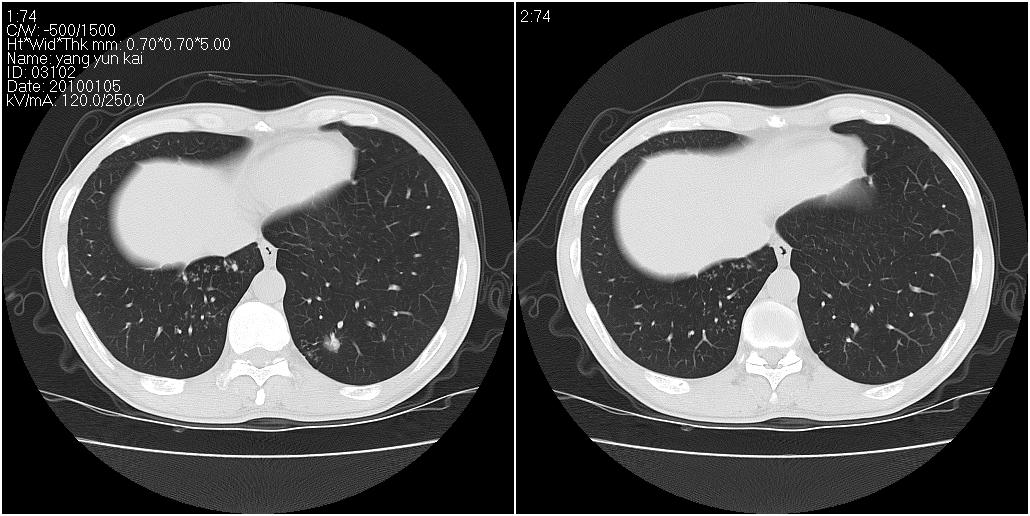

标题: CT23980:男性,47岁。近来咳痰、咳血,血沉增快(40左右),

男性,47岁。近来咳痰、咳血,血沉增快(40左右),痰中未检出结核杆菌。

符合继发性结核表现部分空洞形成并播散